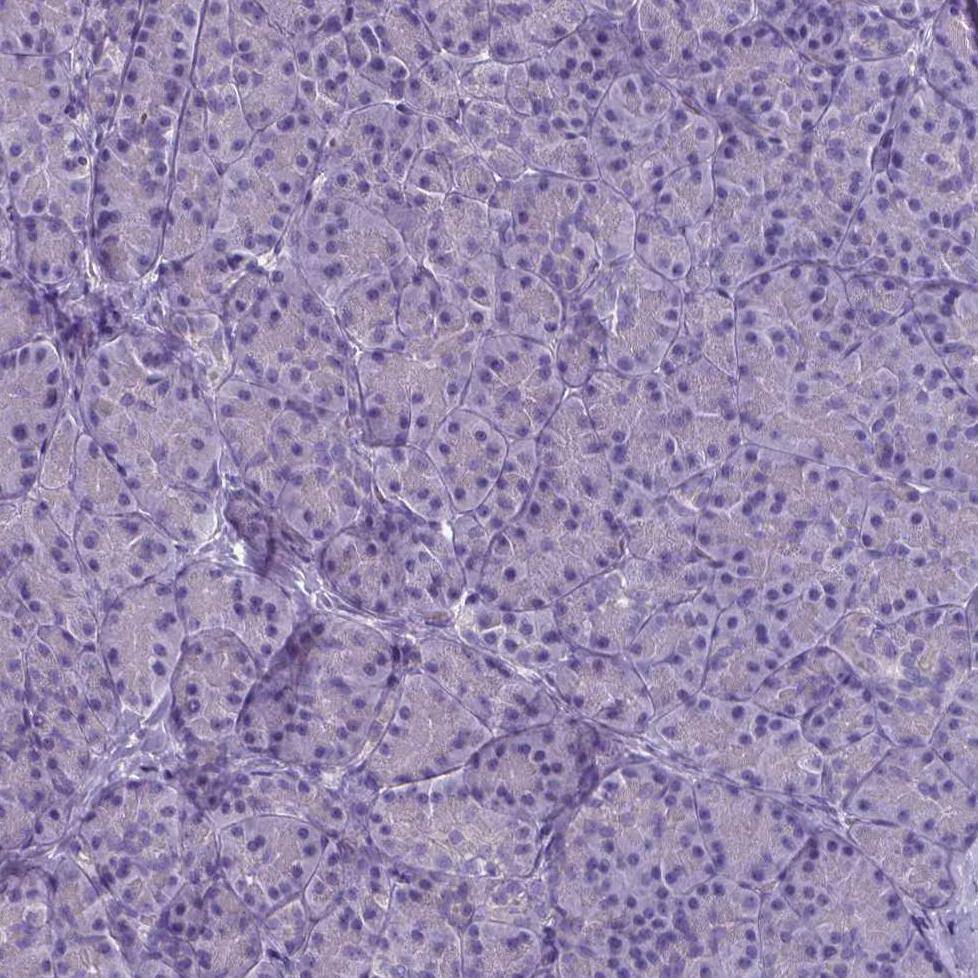

Staining of HeLa cells using the Anti-PLA2R1 monoclonal antibody) .